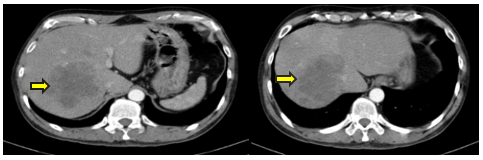

- Cắt lớp vi tính ổ bụng :

Hình 2: Gan phải có khối lớn kèm nhiều nốt nhỏ lân cận, kích thước lớn nhất 87x93mm, ngấm thuốc kém sau tiêm, theo dõi thứ phát.